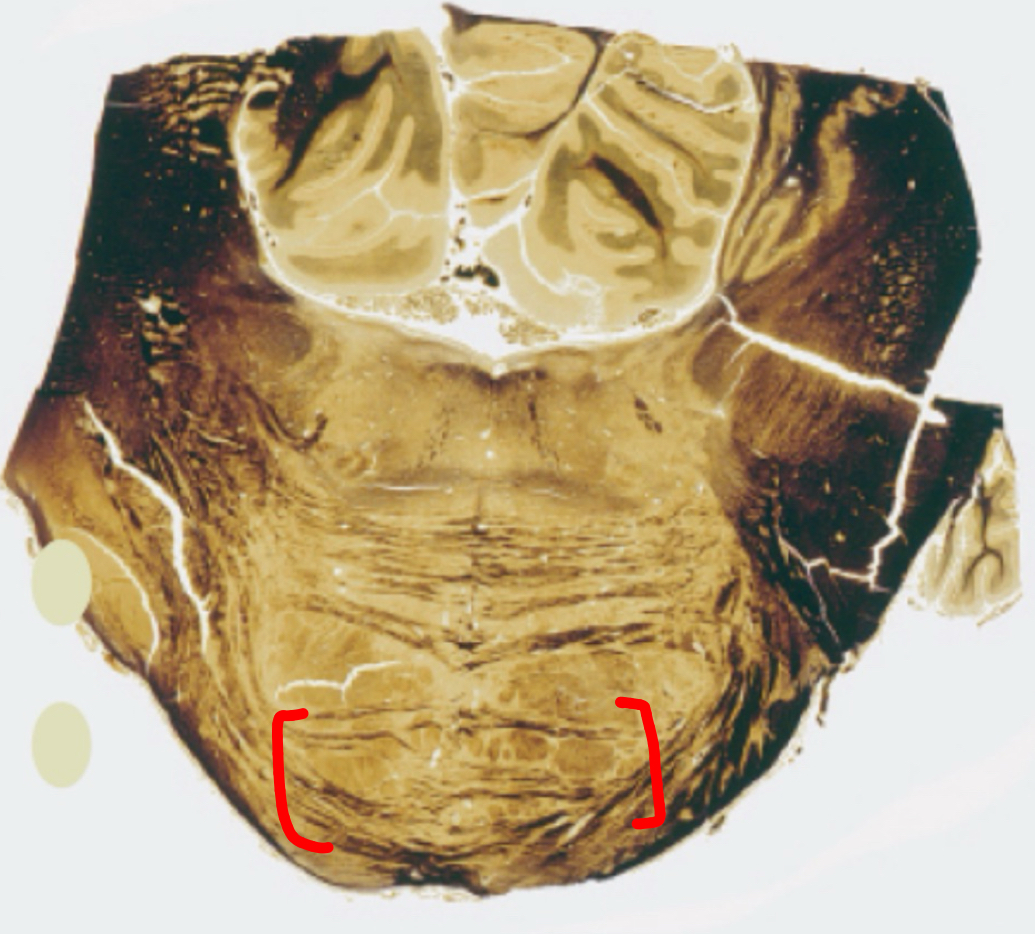

dentate nucleus

posterior lobe

vermis

tonsils

flocculus

nodule

cerebellar peduncles

4th ventricle